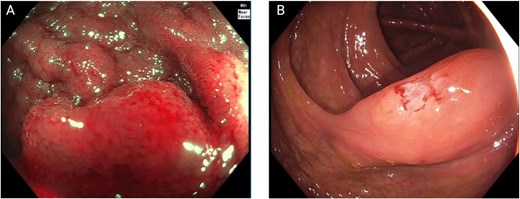

Colonoscopy demonstrated a right-sided subepithelial colonic lesion measuring ⁓30 mm (Fig. 1). Positron emission tomography-computed tomography (PET-CT) revealed circumferential thickening of the ascending colon with intense fluorodeoxyglucose (FDG) uptake (SUVmax 20.0), along with multiple peritoneal implants, mesenteric, perigastric, and right subdiaphragmatic lymphadenopathy, as well as hypermetabolism in the previously identified hepatic lesion (SUVmax 19.8), findings highly suggestive of neoplastic dissemination (Fig. 2).

Colonoscopic findings. (A) Near-focus narrow-band imaging showing a prominent, nodular subepithelial lesion measuring ⁓30 mm, with disrupted mucosal architecture, erythema, and loss of surface vascular pattern—features suggestive of acute mucosal infiltration. (B) Conventional white-light endoscopy demonstrating smooth, elevated mucosa with focal congestion and superficial linear disruption, corresponding to the area of the subepithelial lesion.